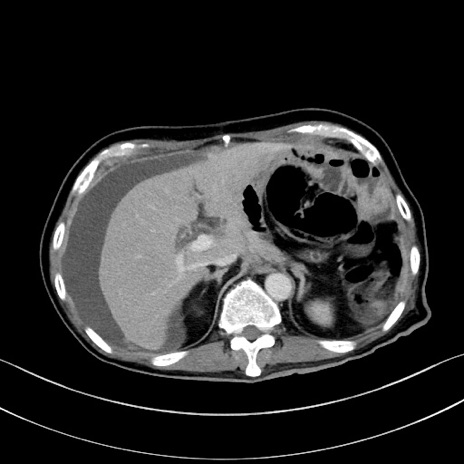

症例28(横断像)

【症例】60歳代男性

【主訴】嘔吐

【現病歴】胃癌にて胃全摘後。食思不振が悪化し、夜中に嘔吐することがある。

【既往歴】胃癌、胃全摘、脾摘、胆摘後

【データ】WBC 5900、CRP 10.56